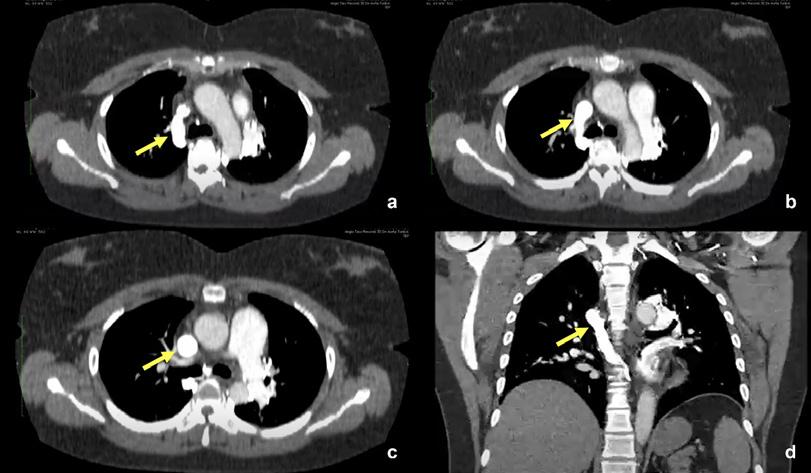

En presencia de una obstrucción en la Vena Cava Superior

a, b, c y

de

Angiotomografía se observan múltiples

hemiácigos accesorio (menor), rodeando el cayado aórtico, que comunican con la vena pulmonar

drenando posteriormente a la aurícula izquierda, generándose así un cortocircuito (de derecha a izquierda) venoso sistémico a venoso pulmonar en forma directa.

(VCS), se vuelve muy importante la formación de vías alternativas para mantener el drenaje venoso. Estas vías ayudan a prevenir un empeoramiento del cuadro clínico del paciente y pueden explicar la aparición de captaciones extrapulmonares del MAA en lugares inusuales como el hígado, el esternón, las vértebras, los arcos costales, el cerebro y los riñones, en un estudio de perfusión pulmonar, como se ha descrito en casos previos (1,2,3).

El desarrollo de esas vías colaterales o alternas ayuda a llevar la sangre venosa de la parte superior del cuerpo hacia el corazón derecho, pudiendo depositarse el MAA en la primera red capilar que encuentra. Algunas de estas vías colaterales son las intercostales superiores e inferiores, la mamaria interna, el sistema venoso vertebral, la vena ácigos y la hemiácigos (2).

En nuestro caso, la visualización de las vértebras torácicas se debe al flujo retrógrado a través del sistema venoso vertebral dilatado, que normalmente lleva la sangre venosa prevertebral al sistema ácigos, y también al nulo drenaje de la médula ósea, donde el MAA queda atrapado (2,4).

Es importante tener en cuenta que el desarrollo de estas vías colaterales puede variar según el nivel de obstrucción y pueden tener diferentes patrones (Tabla 1). La formación de una vía venosa colateral sistémica a pulmonar es una complicación poco común de la obstrucción de la VCS. La presencia de tales vasos colaterales da como resultado un cortocircuito de derecha a izquierda, lo que puede dejar al paciente susceptible a un accidente cerebrovascular, absceso cerebral y un estado de alto gasto cardíaco (4). En nuestro caso, se evidenció un shunt de derecha a izquierda, como se describe en la Fig. 6. Ya que el

Figura 6. En las imágenes

d

la

colaterales del sistema

izquierda,